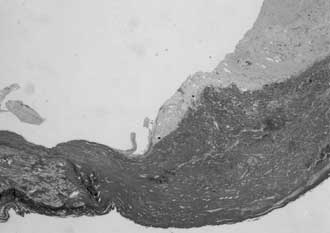

| Fig.

5 |

Pathological

examination of the specimen demonstrated a true aneurysm

with hyaline thickening of the wall. |